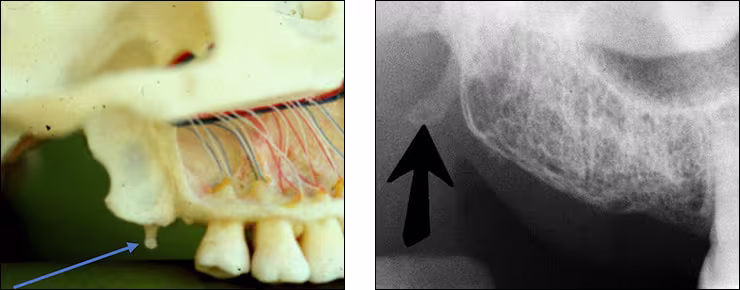

Pterygoid plates – The lateral and medial pterygoid plates are located behind the maxillary tuberosity. They project a single image configured like a thin wing of bone extending posteriorly from the tuberosity. This bilateral radiopacity is occasionally recorded on maxillary molar periapical images when the receptor is positioned adequately posterior.

Hamular process – The hamular process or pterygoid hamulus is a tiny finger or hook-like projection of bone that extends inferiorly from the medial pterygoid plate. This bilateral radiopacity occasionally appears on maxillary molar periapical images and molar bitewings when the receptor is positioned sufficiently posterior to record it.